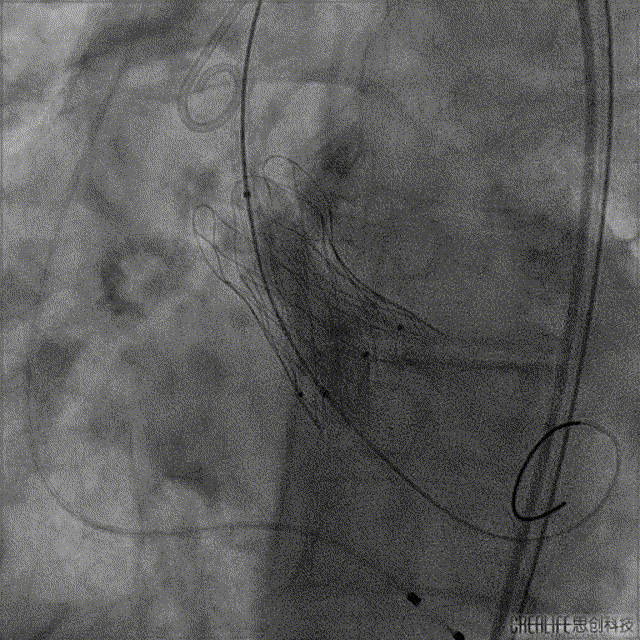

手术过程:

Numed 20mm*40mm 球囊后扩:Video 5

最终效果:Video 6